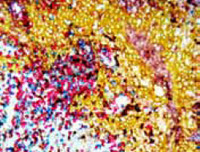

For decades, immunohistochemistry (IHC) has been an invaluable tool for the detection, localization, and quantification of antigens in preserved tissue for research and diagnostic purposes. Enzo’s complete set of tools improve the quality and efficiency of your IHC process from start to finish. Avoid ambiguity with high-sensitivity and low background reagents that are compatible with manual and automated platforms. Combined with the market’s most extensive palette of unique chromogens, Enzo provides the flexibility needed for simple or complex protocols.

- High intensity color development delivers sharp, crisp staining

POLYVIEW® PLUS detection reagents are ready-to-use (RTU), biotin-free solutions developed by directly labeling immunoglobulins (anti-mouse or anti-rabbit) with a nanopolymer of alkaline phosphatase (AP) or horseradish peroxidase (HRP) using proprietary technology. This ensures consistent and reproducible immunodetection of primary antibodies (mouse or rabbit) or nucleic acid probes combined with label (digoxigenin or biotin) linker against nuclear, cytoplasmic and membrane antigens in different types of tissue specimens. The single-step IHC or two-step ISH methodology enables faster staining procedures with significantly lower background.